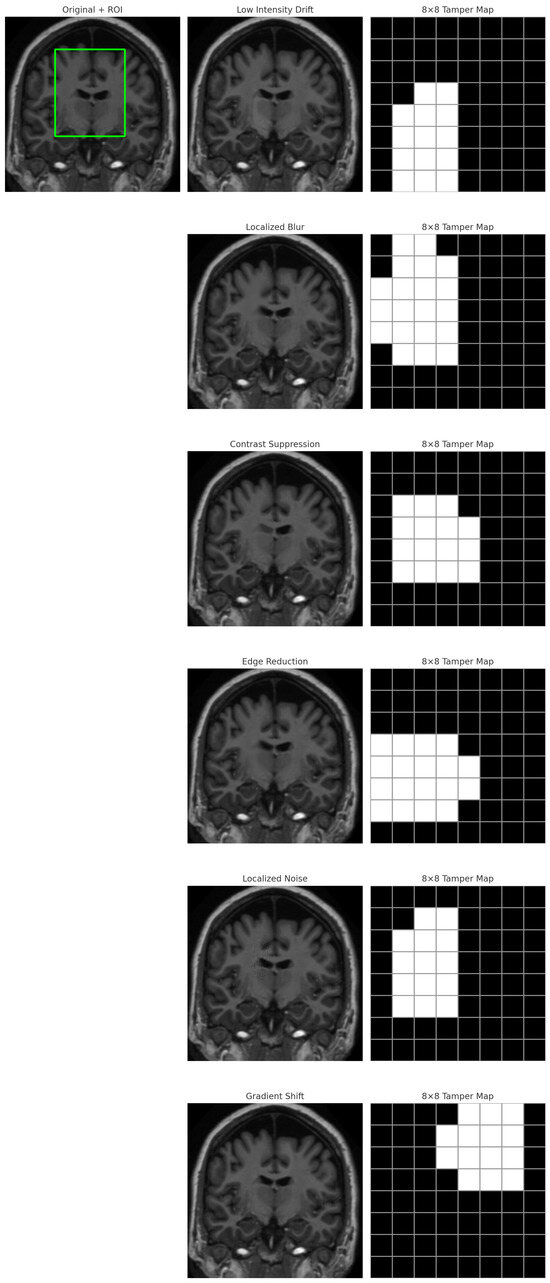

A Non-Embedding Watermarking Framework Using MSB-Driven Reference Mapping for Distortion-Free Medical Image Authentication

Ensuring the integrity of medical images is essential to securing clinical workflows, telemedicine platforms, and healthcare IoT environments. Existing watermarking and reversible data-hiding approaches often modify pixel intensities, reducing diagnostic fidelity, introducing embedding constraints, or causing instability under compression and format conversion. This [...] Read more.

Ensuring the integrity of medical images is essential to securing clinical workflows, telemedicine platforms, and healthcare IoT environments. Existing watermarking and reversible data-hiding approaches often modify pixel intensities, reducing diagnostic fidelity, introducing embedding constraints, or causing instability under compression and format conversion. This work proposes a distortion-free, non-embedding authentication framework that leverages the inherent stability of the most significant bit (MSB) patterns in the Non-Region of Interest (NROI) to construct a secure and tamper-sensitive reference for the diagnostic Region of Interest (ROI). The ROI is partitioned into fixed blocks, each producing a 256-bit SHA-256 signature. Instead of embedding this signature, each hash bit is mapped to an NROI pixel whose MSB matches the corresponding bit value, and only the encrypted coordinates of these pixels are stored externally in a secure database. During verification, hashes are recomputed and compared bit-by-bit with the MSB sequence extracted from the referenced NROI coordinates, enabling precise block-level tamper localization without modifying the image. Extensive experiments conducted on MRI (OASIS), X-ray (ChestX-ray14), and CT (CT-ORG) datasets demonstrate the following: (i) perfect zero-distortion fidelity; (ii) stable and deterministic MSB-class mapping with abundant coordinate diversity; (iii) 100% detection of intentional ROI tampering with no false positives across the six clinically relevant manipulation types; and (iv) robustness to common benign Non-ROI operations. The results show that the proposed scheme offers a practical, secure, and computationally lightweight solution for medical image integrity verification in PACS systems, cloud-based archives, and healthcare IoT applications, while avoiding the limitations of embedding-based methods. Full article